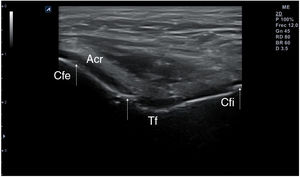

Punciones ecoguiadas en medicina familiar52–59Técnica de exploraciónPara realizar punciones superficiales, es preferible el uso de la sonda lineal de alta frecuencia por su mejor resolución superficial. Así, los accesos vasculares, los bloqueos neurales o las infiltraciones articulares, se beneficiarán de una guía visual de alta definición que permita una buena imagen de las estructuras menos profundas. En los drenajes de gran cantidad de fluido, o lesiones en profundidad, está indicado el uso de la sonda convexa de baja frecuencia. La toracocentesis o la paracentesis (en nuestro caso generalmente diagnósticas y rara vez terapéuticas) se beneficiarán del uso de esta sonda.

La punción se puede hacer en el eje largo de la sonda, denominada también «en plano» (fig. 14), con la aguja entre 30 y 45° de inclinación respecto a la superficie, lo que permite visualizarla en todo su trayecto, y lo hace muy recomendable cuando haya riesgo de lesionar estructuras cercanas. La aguja aparecerá en la pantalla como una línea hiperecogénica brillante con artefacto de reverberación (al ser un objeto metálico, se dibujarán líneas paralelas hiperecogénicas por debajo de la misma por un efecto espejo). Para poder visualizar correctamente todo el trayecto de la aguja, esta debe orientarse en el mismo plano de corte de la sonda.

En otros casos interesará realizar un abordaje en el eje corto de la sonda, denominado «fuera de plano»(fig. 15) introduciendo la aguja perpendicular a la sonda, en su parte media, de modo que en la pantalla será visible únicamente la punta. Esta técnica no permite seguir el trayecto completo de la aguja en un solo corte, pero ofrece una imagen precisa de su punta. El uso de una u otra técnica dependerá de las preferencias del profesional que realice la técnica, del tipo de punción y de las condiciones anatómicas de la zona.